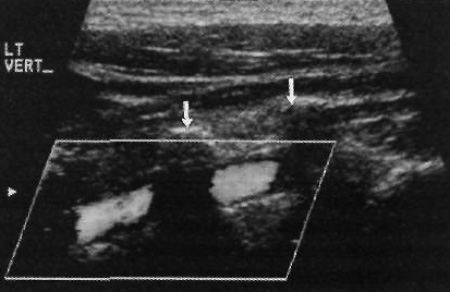

Как правило, используют датчик с частотой 7,5 МГц. Если шея большая, для проведения цветовой допплерографии позвоночных артерий нужна большая проникающая способность – в этом случае применяют датчик с частотой 5 МГц. Датчик можно располагать в плоскости теней от поперечных отростков. Независимо от локализации можно визуализировать только один сегмент артерии (фото 14).

Фото 14. Позвоночная артерия в норме. Кровоток направлен к голове (в данном случае – от датчика). Стрелками обозначены поперечные отростки позвоночника, которые препятствуют нормальной визуализации артерий в отверстиях позвонков